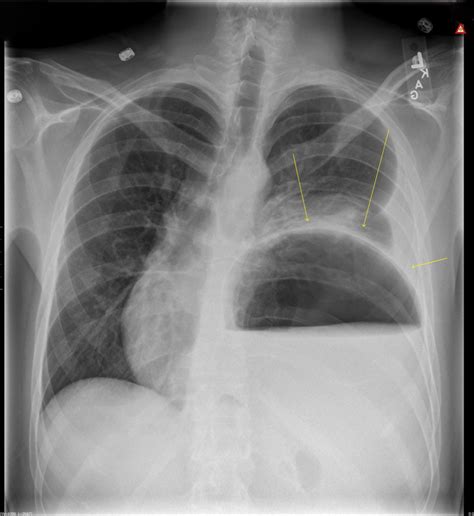

• Imaging Tests: X-rays, CT scans, or MRIs can provide detailed images of the chest cavity, helping to identify any structural abnormalities or inflammation.